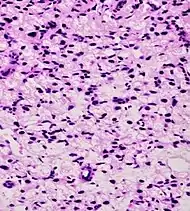

- Relatively common and highly specific

- [4]

- Multiple nucleoli

- Eccentric nucleoli[4]

- Acinar adenocarcinoma with multiple nucleoli.

- Acinar adenocarcinoma with double and eccentric nucleoli.